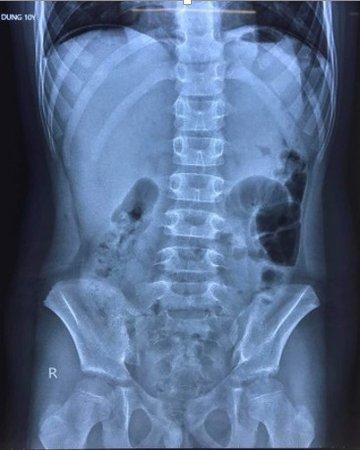

Theo hình ảnh chụp X-quang, bệnh nhi có liềm hơi dưới vòm hoành 2 bên. Tại Bệnh viện Trẻ em, bé được chẩn đoán bị viêm phúc mạc do thủng dạ dày/mắc Covid-19.

Hình ảnh chụp X-quang cho thấy bệnh nhi có liềm hơi dưới vòm hoành 2 bên, bác sĩ nghi thủng tạng rỗng. Ảnh: Bệnh viện Trẻ em Hải Phòng cung cấp.